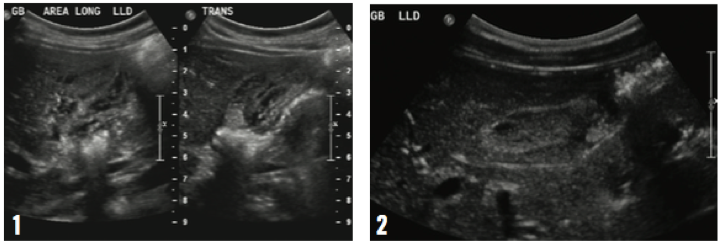

Ultrasonography of the abdomen revealed a necrotic gallbladder with thickened wall, septations, and pericholecystic fluid. However, there were no stones, and the appearances of the liver and spleen were unremarkable (Figure 1). The boy was treated symptomatically with hydration, pain control with acetaminophen, and a vegetarian diet. He improved after several days in the hospital, and 2 weeks after discharge his liver enzyme and bilirubin levels were within reference ranges, and repeat ultrasonography results were unremarkable.

His 13-year-old sister developed nausea, anorexia, abdominal pain, and jaundice without fever about 2 weeks after her brother’s presentation. She had received the hepatitis A vaccine for an unimmunized household contact 2 weeks earlier. Her laboratory test results showed elevated liver enzymes (ALT, 2473 U/L; AST, 2107 U/L), a total bilirubin level of 6.3 mg/dL, a direct bilirubin level of 5.3 mg/dL, and positive results for serum IgM antibodies to hepatitis A virus. Her abdominal ultrasonography results were similar to those of her brother, and both were consistent with acalculous cholecystitis (Figure 2). The girl was managed symptomatically at home. Four weeks later, laboratory test results showed that her liver enzymes and bilirubin levels were unremarkable. Her repeat ultrasonography results were also unremarkable.